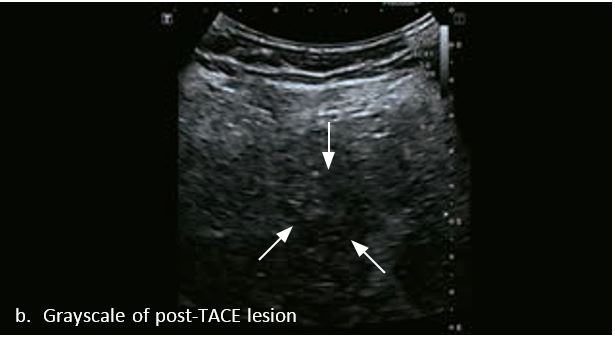

Оцінка результатів лікування ГЦК

Проведено повторне обстеження 79-річного чоловіка з цирозом печінки В, ускладненим ГЦК, після транс-артеріальної хіміоемболізації (ТАХЕ). Було виявлено нове ураження, розташоване поруч з ураженням після ТАХЕ. На сірошкальному зображенні чітко видно нове ураження, але складно виявити рецидив ГЦК в зоні ураження після ТАХЕ. За допомогою кольорового картування SMI (cSMI) можна побачити розвинену судинну мережу всередині нового вогнища ураження. Для оцінки результату лікування було виконано CEUS. За допомогою CEUS можна легко дослідити як нове ураження, так і рецидив ГЦК у вогнищі ураження після TACE. Нове ураження демонструє гіперпосилення артеріальної фази і відсутність вимивання до 5 хвилин, отже, це ураження LI-RADS 4, ймовірна ГЦК за критеріями LI-RADS. Підживлюючі судини можна чітко спостерігати в ранній артеріальній фазі. Для ураження після TACE, більша його частина не підсилюється, однак, в артеріальній фазі спостерігається ділянка гіперпосилення у верхній частині лікованого ураження, що вказує на рецидив ГЦК.

Малюнок 10